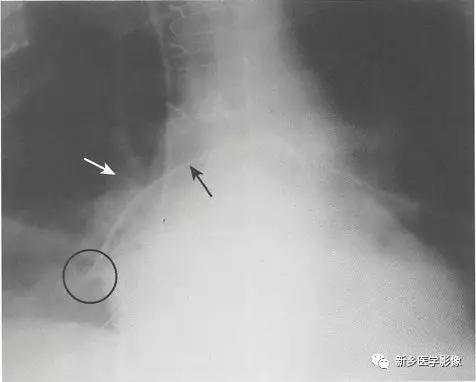

肺动脉导管: 漂浮导管

漂浮导管的正确位置(也称为肺毛细血管楔压管)

●漂浮导管与中心静脉导管外形相似,但长一些。

●通过锁骨下静脉或颈内静脉插入,管头漂浮进入右或左肺动脉的近端。漂浮导管的管头距肺门不应超过2cm。

●只在测量压力时导管气囊暂时充气,过后放气。

漂浮导管的位置异常与并发症。

●少见严重并发症。

●最常见的严重并发症是由于导管或由导管引发的血栓造成肺动脉闭塞,引起肺梗死。

●外周置管可引起局部的局限的穿孔或形成假性动脉瘤,假性动脉瘤表现为重症监护患者在管头位置有实变或肿块,患者也可有咯血。

●应确定导管管头不位于肺动脉的远端分支内,因为异位会增加并发症发生的风险。